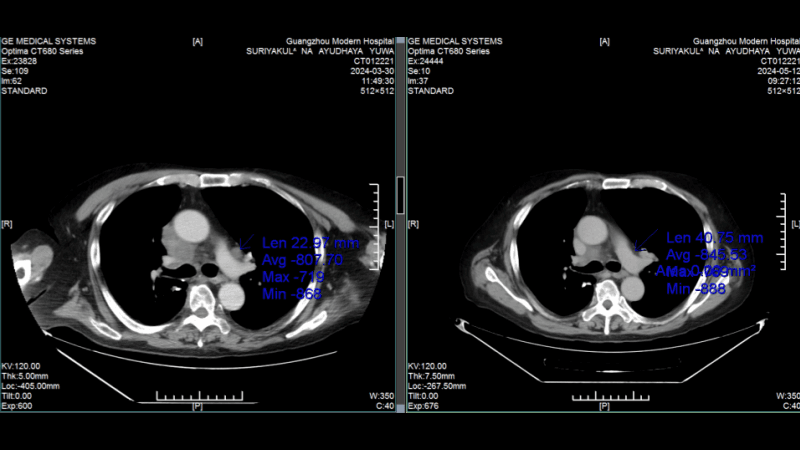

КТ-снимки подтвердили: динамика положительная, болезнь отступает

26 февраля 2024 года результаты КТ показали, что опухоль легкого значительно уменьшилась